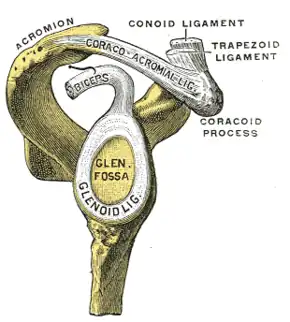

| |

| Glenoid fossa of right side. (Glenoidal labrum labeled as "glenoid lig.") | |

A SLAP tear or SLAP lesion is an injury to the superior glenoid labrum (fibrocartilaginous rim attached around the margin of the glenoid cavity in the shoulder blade) that initiates in the back of the labrum and stretches toward the front into the attachment point of the long head of the biceps tendon. SLAP is an acronym for "Superior Labrum Anterior and Posterior".[1] SLAP lesions are commonly seen in overhead throwing athletes but middle-aged labor workers can also be affected, and they can be caused by chronic overuse or an acute stretch injury of the shoulder.[2]

The shoulder joint is a "ball-and-socket" joint.[5] However, the 'socket' (the glenoid fossa of the scapula) is small, covering at most only a third of the 'ball' (the head of the humerus). It is deepened by a circumferential rim of fibrocartilage, the glenoidal labrum. Previously there was debate as to whether the labrum was fibrocartilaginous as opposed to hyaline cartilage found in the remainder of the glenoid fossa. Previously, it was considered a redundant, evolutionary remnant, but is now considered integral to shoulder stability. Most agree that the proximal tendon of the long head of the biceps brachii muscle becomes fibrocartilaginous prior to attaching to the superior aspect of the glenoid. The long head of the triceps brachii inserts inferiorly, similarly.[6] Together, all of those cartilaginous extensions are termed the 'glenoid labrum'.